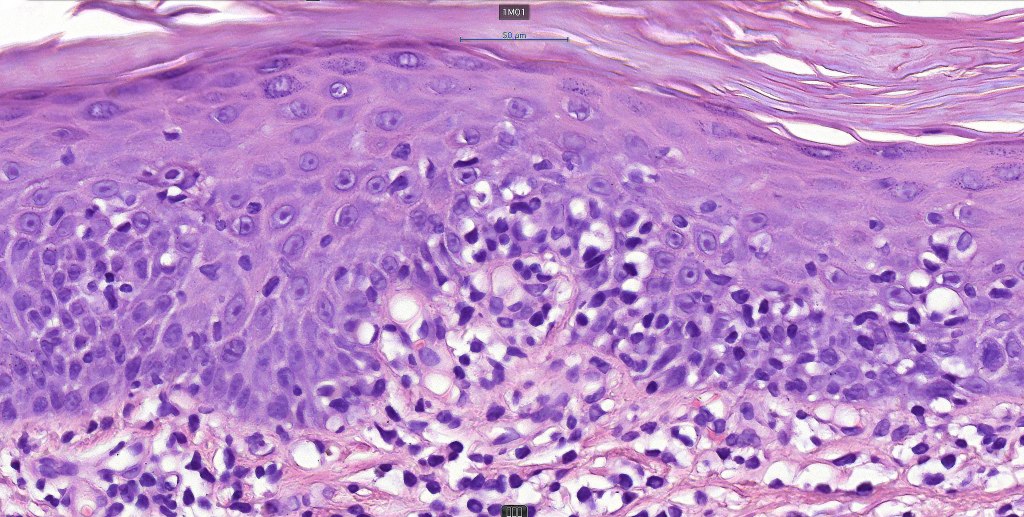

Histological features

The histological hallmark of mycosis fungoides is the presence of large atypical lymphocytes with a convoluted/cerebriform nuclear border (Sézary cells). These may be found at the epidermal-dermal jnuction and as collections within the epidermis (Pautrier microabscess). These are most easily found in plaque stage disease. The epidermal component can be subtle in patch stage disease and is often lost in tumor stage dsease. The classification into patch, plaque & tumor stage disease is less helpful histologically as the features merge from one to the other. It is all a matter of degree.

Plaque Stage Disease

•Compact hyperkeratosis & patchy parakeratosis

•Acanthosis

•Psoriasiform hyperplasia common

•Epidermotropism is often marked with conspicuous Pautrier microabscesses

•Lichenoid variant & poikiloderma atrophicans vasculare

•Variable folliculotropism (+/- mucinosis) & syringotropism

•Coarse collagen bundles in papillary dermis

•Superficial band-like dermal infiltrate of atypical lymphocytes, eosinophils, plasma cells & histiocytes